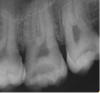

En 2013 concurre paciente de sexo femenino de 37 años de edad a la Clínica Integrada II UdelaR por caries profunda en pieza 37 (Fig. 2a). Se diagnostica CPPA ya que solo el test de fresado da positivo. Se planifica eliminación total de caries de paredes laterales con aislación absoluta. Se observa último test colorimétrico con rojo ácido 52 en propilenglicol (Detector, Pharma Dent, Uruguay) dejando fina capa de dentina infectada en pared axial (Fig. 2b) la cual se protege con mezcla de hidróxido de calcio (Ca(OH)2) puro con suero fisiológico y luego encima Ca(OH)2 fraguable (Life, Kerr, USA) (Fig. 2c). Se sella con ionómero vítreo (Gold Label Luting & Lining Cement, Tokyo, Japan).